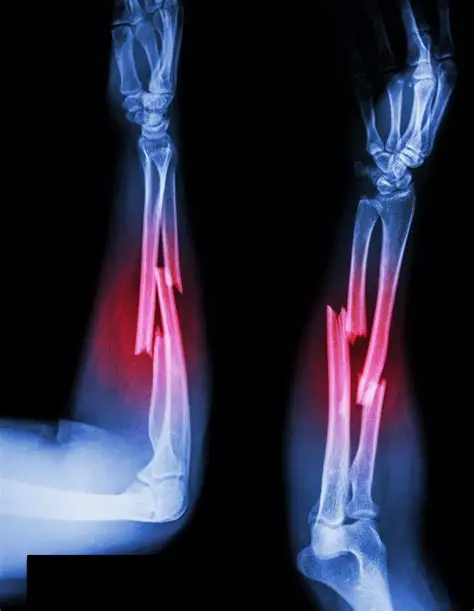

Forearm fracture is the fracture, which occurs between the wrist and the elbow. The bones which get fractured are the radius and the ulna. Radius bone lies on the thumb side of the forearm whereas the ulna bone lies on the little finger side.

X-rays: X-rays show clear images of the bones and help to determine the extent of the injury.